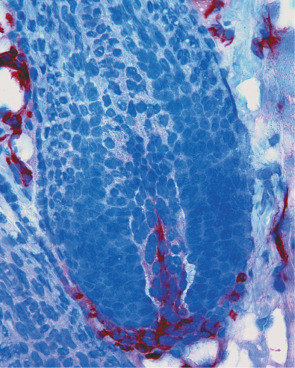

At the ultrastructural level, vascular endothelial cells are characterized by tight junctions between neighboring cells and by specialized organelles, the rod-shaped Weibel–Palade bodies ( Fig. 102.5 ), that serve as storage organelles for the coagulation factor von Willebrand factor, also known as factor VIII-related antigen. Weibel–Palade bodies also contain P-selectin, angiopoietin-2, and endothelin-1. Activation of endothelial cells by proinflammatory cytokines or pro-angiogenic factors readily leads to translocation of these storage organelles to the cell membrane, with consecutive enhanced membrane expression of P-selectin and release of von Willebrand factor. Other characteristic ultrastructural features include caveolae (minute invaginations of the membrane surface), pinocytotic vesicles, and the formation of vesiculo-vacuolar organelles (VVOs) . Circulating macromolecules cross the endothelium through interendothelial cell gaps and transendothelial cell pores, some of which arise from VVOs. Endothelial cell fenestrations, areas with direct apposition of the endothelial cell membranes without intervening cytoplasm, are rarely seen in normal skin except in angiogenic perifollicular blood vessels during the growth phase of the hair follicle. However, fenestrated endothelial cells are frequently seen in skin diseases with pronounced angiogenesis and vascular hyperpermeability, including psoriasis.